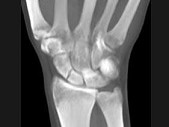

- 单项选择题男,21岁, 手部不慎摔伤,局部疼痛, 结合图像,最可能的诊断是 ( )

A、大多角骨骨折

B、小多角骨骨折

C、三角骨骨折

D、月骨骨折

E、舟状骨骨折